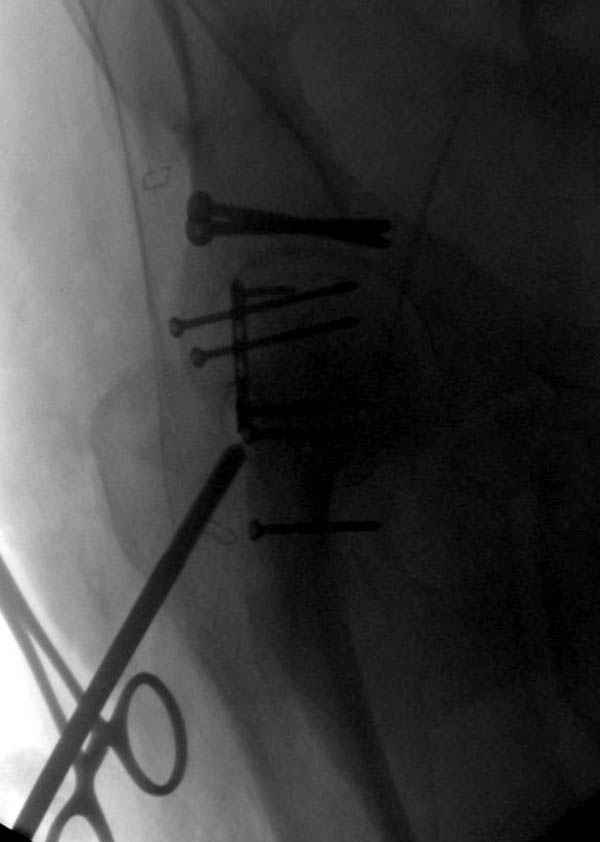

По снимку создается впечатление о высоком поперечном переломе, задней колонны, стенки; почему не пользовались *magic screw*?

Латеральное положение облегчает проведение тракции через вертел, за 5 мм стержень за вертел (грузом через тракционное приспособление), на обычном рентгенопрозрачном операционном столе, а для положения на животе, наверное, Judet Table более приемлем, потому что там имеется латеральное тракционное устроиство.

Там множество обычных 2.7 мм шурупов, потом идет фиксация основными пластинами.

Снимки здесь....